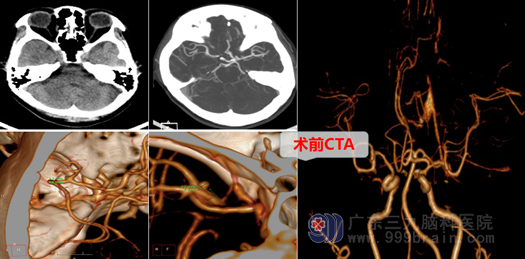

患者吕某3天前无明显诱因出现剧烈头痛并伴有呕吐,且出现意识障碍、肢体偏瘫等不适症状,家人感觉情况严重而紧急,慌忙拨打120急救电话,救护车很快将其接到当地医院。当地医院急查头颅CT,报告:大脑中动脉分叉处动脉瘤破裂出血,情况紧急,为了救命,家人将其急转入更专业的三九脑科医院求治。

吕某转入后,经欧阳辉主任带领神经外十科团队讨论后,决定尽快给患者吕某采取外科直接开颅手术,行“右侧大脑中动脉M1段分叉处动脉瘤夹闭术”进行抢救、治疗,他们以“生命至上”的理念,迅速在全麻下切开头皮,翻开皮瓣。切开、剥离颞肌、骨膜,骨瓣开颅后,在显微镜下分开侧裂,仔细寻找大脑中动脉M1、分叉及其M2段等,在分叉处见到囊状动脉瘤,大小约2.6mm,瘤顶指向外侧,欧阳主任剑胆琴心,用一枚动脉瘤夹精准地直接夹闭了动脉瘤颈;检查中动脉上、下干均通畅,局部无活动性出血,脑组织及血管保护良好,脑搏动良好,手术过程顺利,达到手术目的。术后返回监护室,患者返病房后神志清醒,四肢肌力肌张力正常。吕某脱离了危险,幸运地逃过一劫。